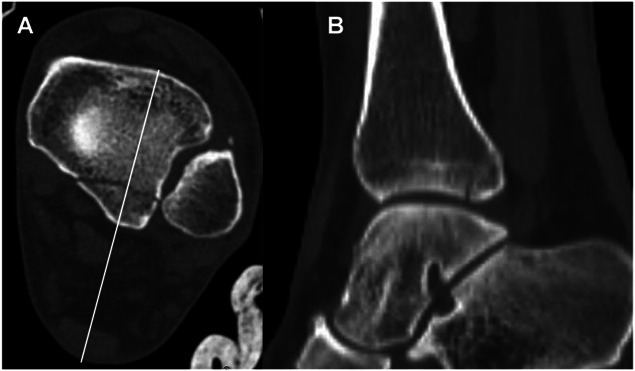

后踝骨骨折(PMFs)(OTA 43B1.1)经常与腓骨、内侧踝骨和胫骨远端骨折同时发生,很少单独出现。PMF 会影响踝关节臼的对齐和巩膜的稳定性。用于固定PMF的技术包括通过后外侧或后内侧方法进行开放复位内固定,或进行前后螺钉固定。对于选定的微移位或无移位的后踝骨骨折,我们开发了一种经皮技术,通过跟腱插入后至前插管螺钉。本文对该技术进行了描述,并回顾了一系列临床案例。

Posterior malleolus fractures (PMFs) (OTA 43B1.1) are frequently seen in combination with fractures of the fibula, medial malleolus, and distal tibia; they can rarely be seen in isolation. PMFs affect the alignment of the ankle mortise and the stability of syndesmosis. Techniques described for fixation of PMFs include open reduction internal fixation through a posterolateral or posteromedial approach or anterior-to-posterior screw fixation. For selected minimally displaced or nondisplaced fractures of the posterior malleolus, we developed a percutaneous technique through the Achilles tendon for the insertion of a posterior-to-anterior cannulated screw. The technique is described, and a clinical series is reviewed.